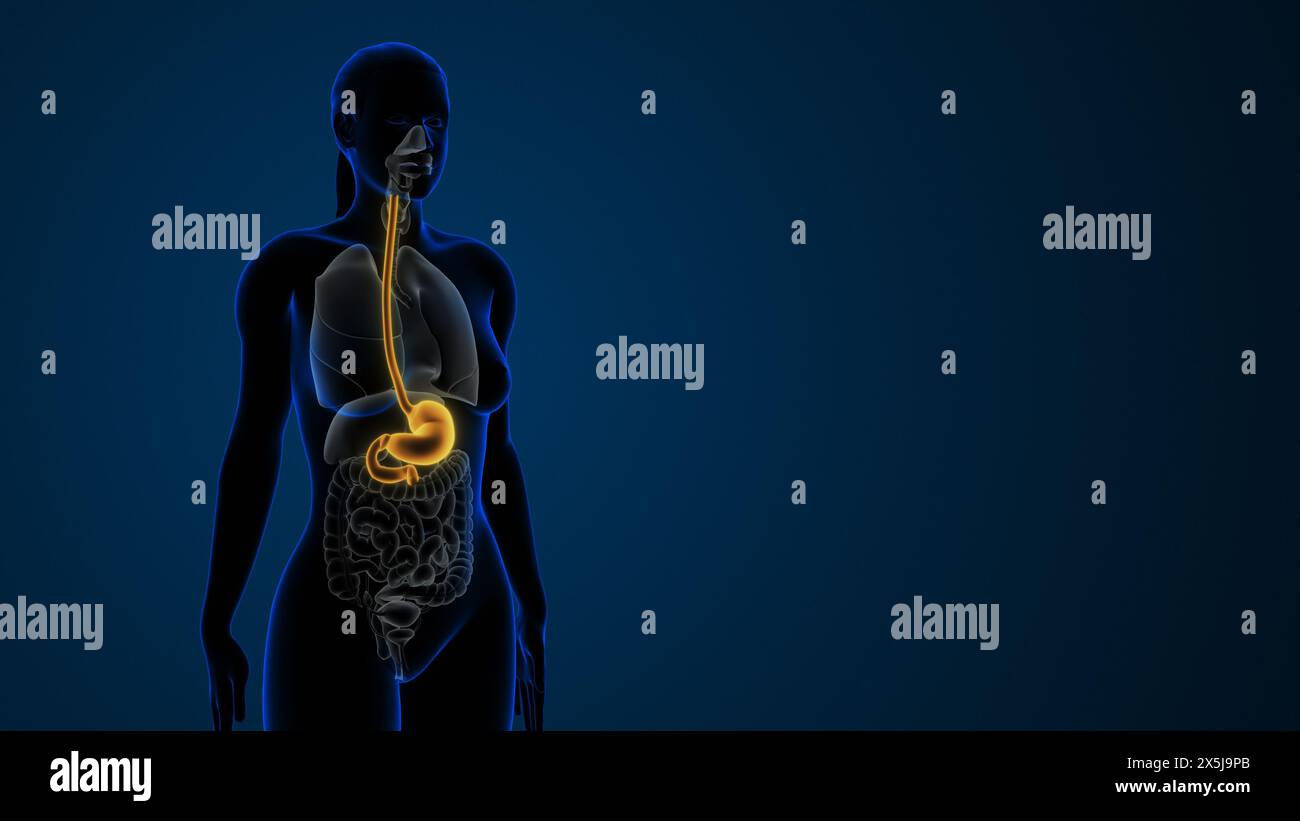

Estomac mis en évidence dans le système digestif féminin Banque D'Imageshttps://www.alamyimages.fr/image-license-details/?v=1https://www.alamyimages.fr/estomac-mis-en-evidence-dans-le-systeme-digestif-feminin-image605838979.html

Estomac mis en évidence dans le système digestif féminin Banque D'Imageshttps://www.alamyimages.fr/image-license-details/?v=1https://www.alamyimages.fr/estomac-mis-en-evidence-dans-le-systeme-digestif-feminin-image605838979.htmlRF2X5J9PB–Estomac mis en évidence dans le système digestif féminin

Estomac mis en évidence dans le système digestif féminin Banque D'Imageshttps://www.alamyimages.fr/image-license-details/?v=1https://www.alamyimages.fr/estomac-mis-en-evidence-dans-le-systeme-digestif-feminin-image605837360.html

Estomac mis en évidence dans le système digestif féminin Banque D'Imageshttps://www.alamyimages.fr/image-license-details/?v=1https://www.alamyimages.fr/estomac-mis-en-evidence-dans-le-systeme-digestif-feminin-image605837360.htmlRF2X5J7MG–Estomac mis en évidence dans le système digestif féminin

Estomac mis en évidence dans le système digestif féminin Banque D'Imageshttps://www.alamyimages.fr/image-license-details/?v=1https://www.alamyimages.fr/estomac-mis-en-evidence-dans-le-systeme-digestif-feminin-image605837554.html

Estomac mis en évidence dans le système digestif féminin Banque D'Imageshttps://www.alamyimages.fr/image-license-details/?v=1https://www.alamyimages.fr/estomac-mis-en-evidence-dans-le-systeme-digestif-feminin-image605837554.htmlRF2X5J7YE–Estomac mis en évidence dans le système digestif féminin